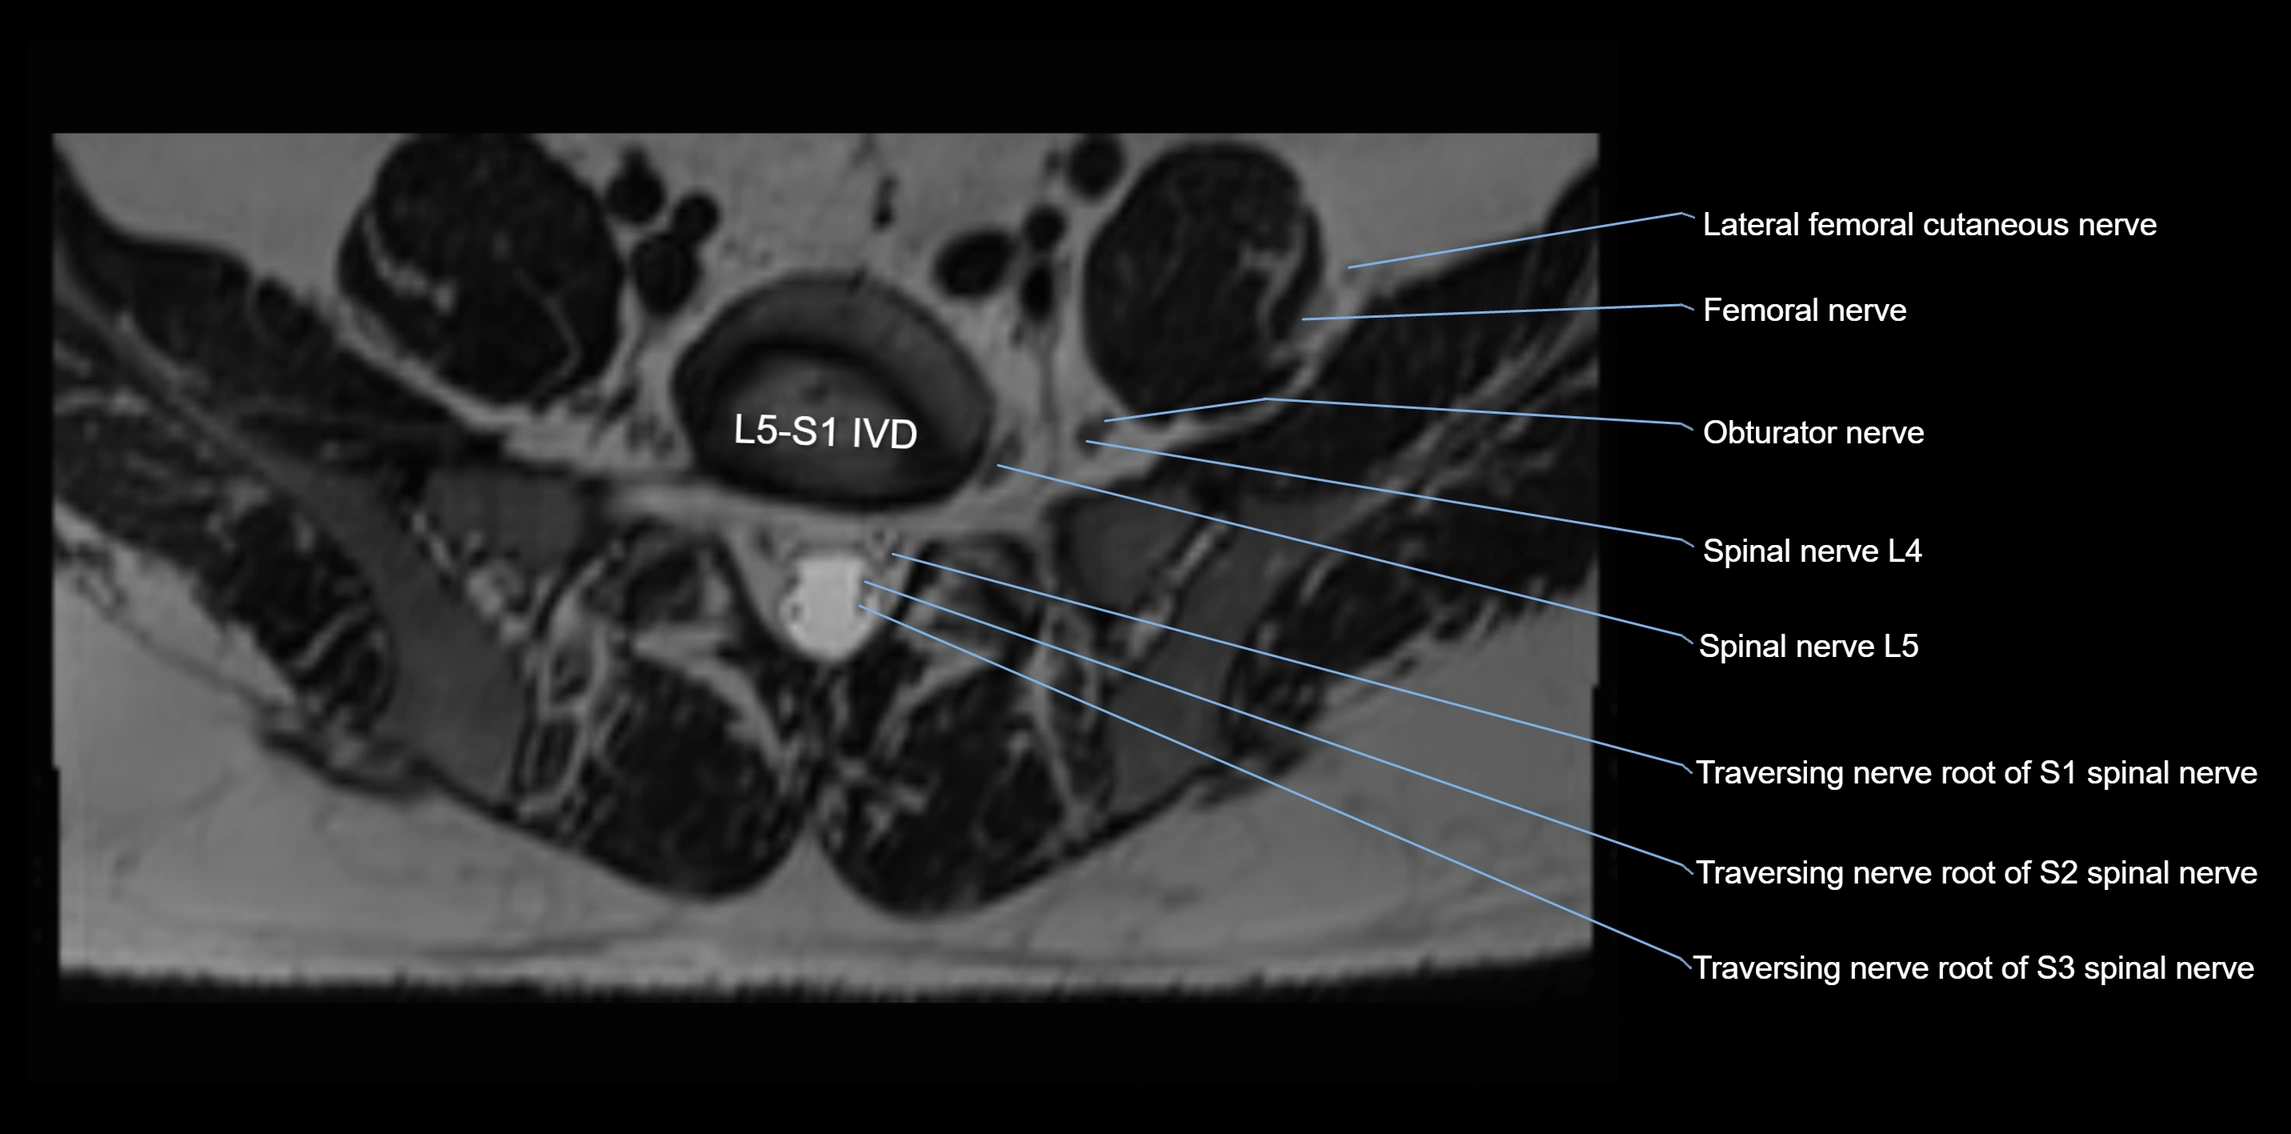

MRI image

image